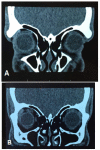

Fig. 3A,B

Computed tomography of orbit showing preservation of structures external to the eyeball